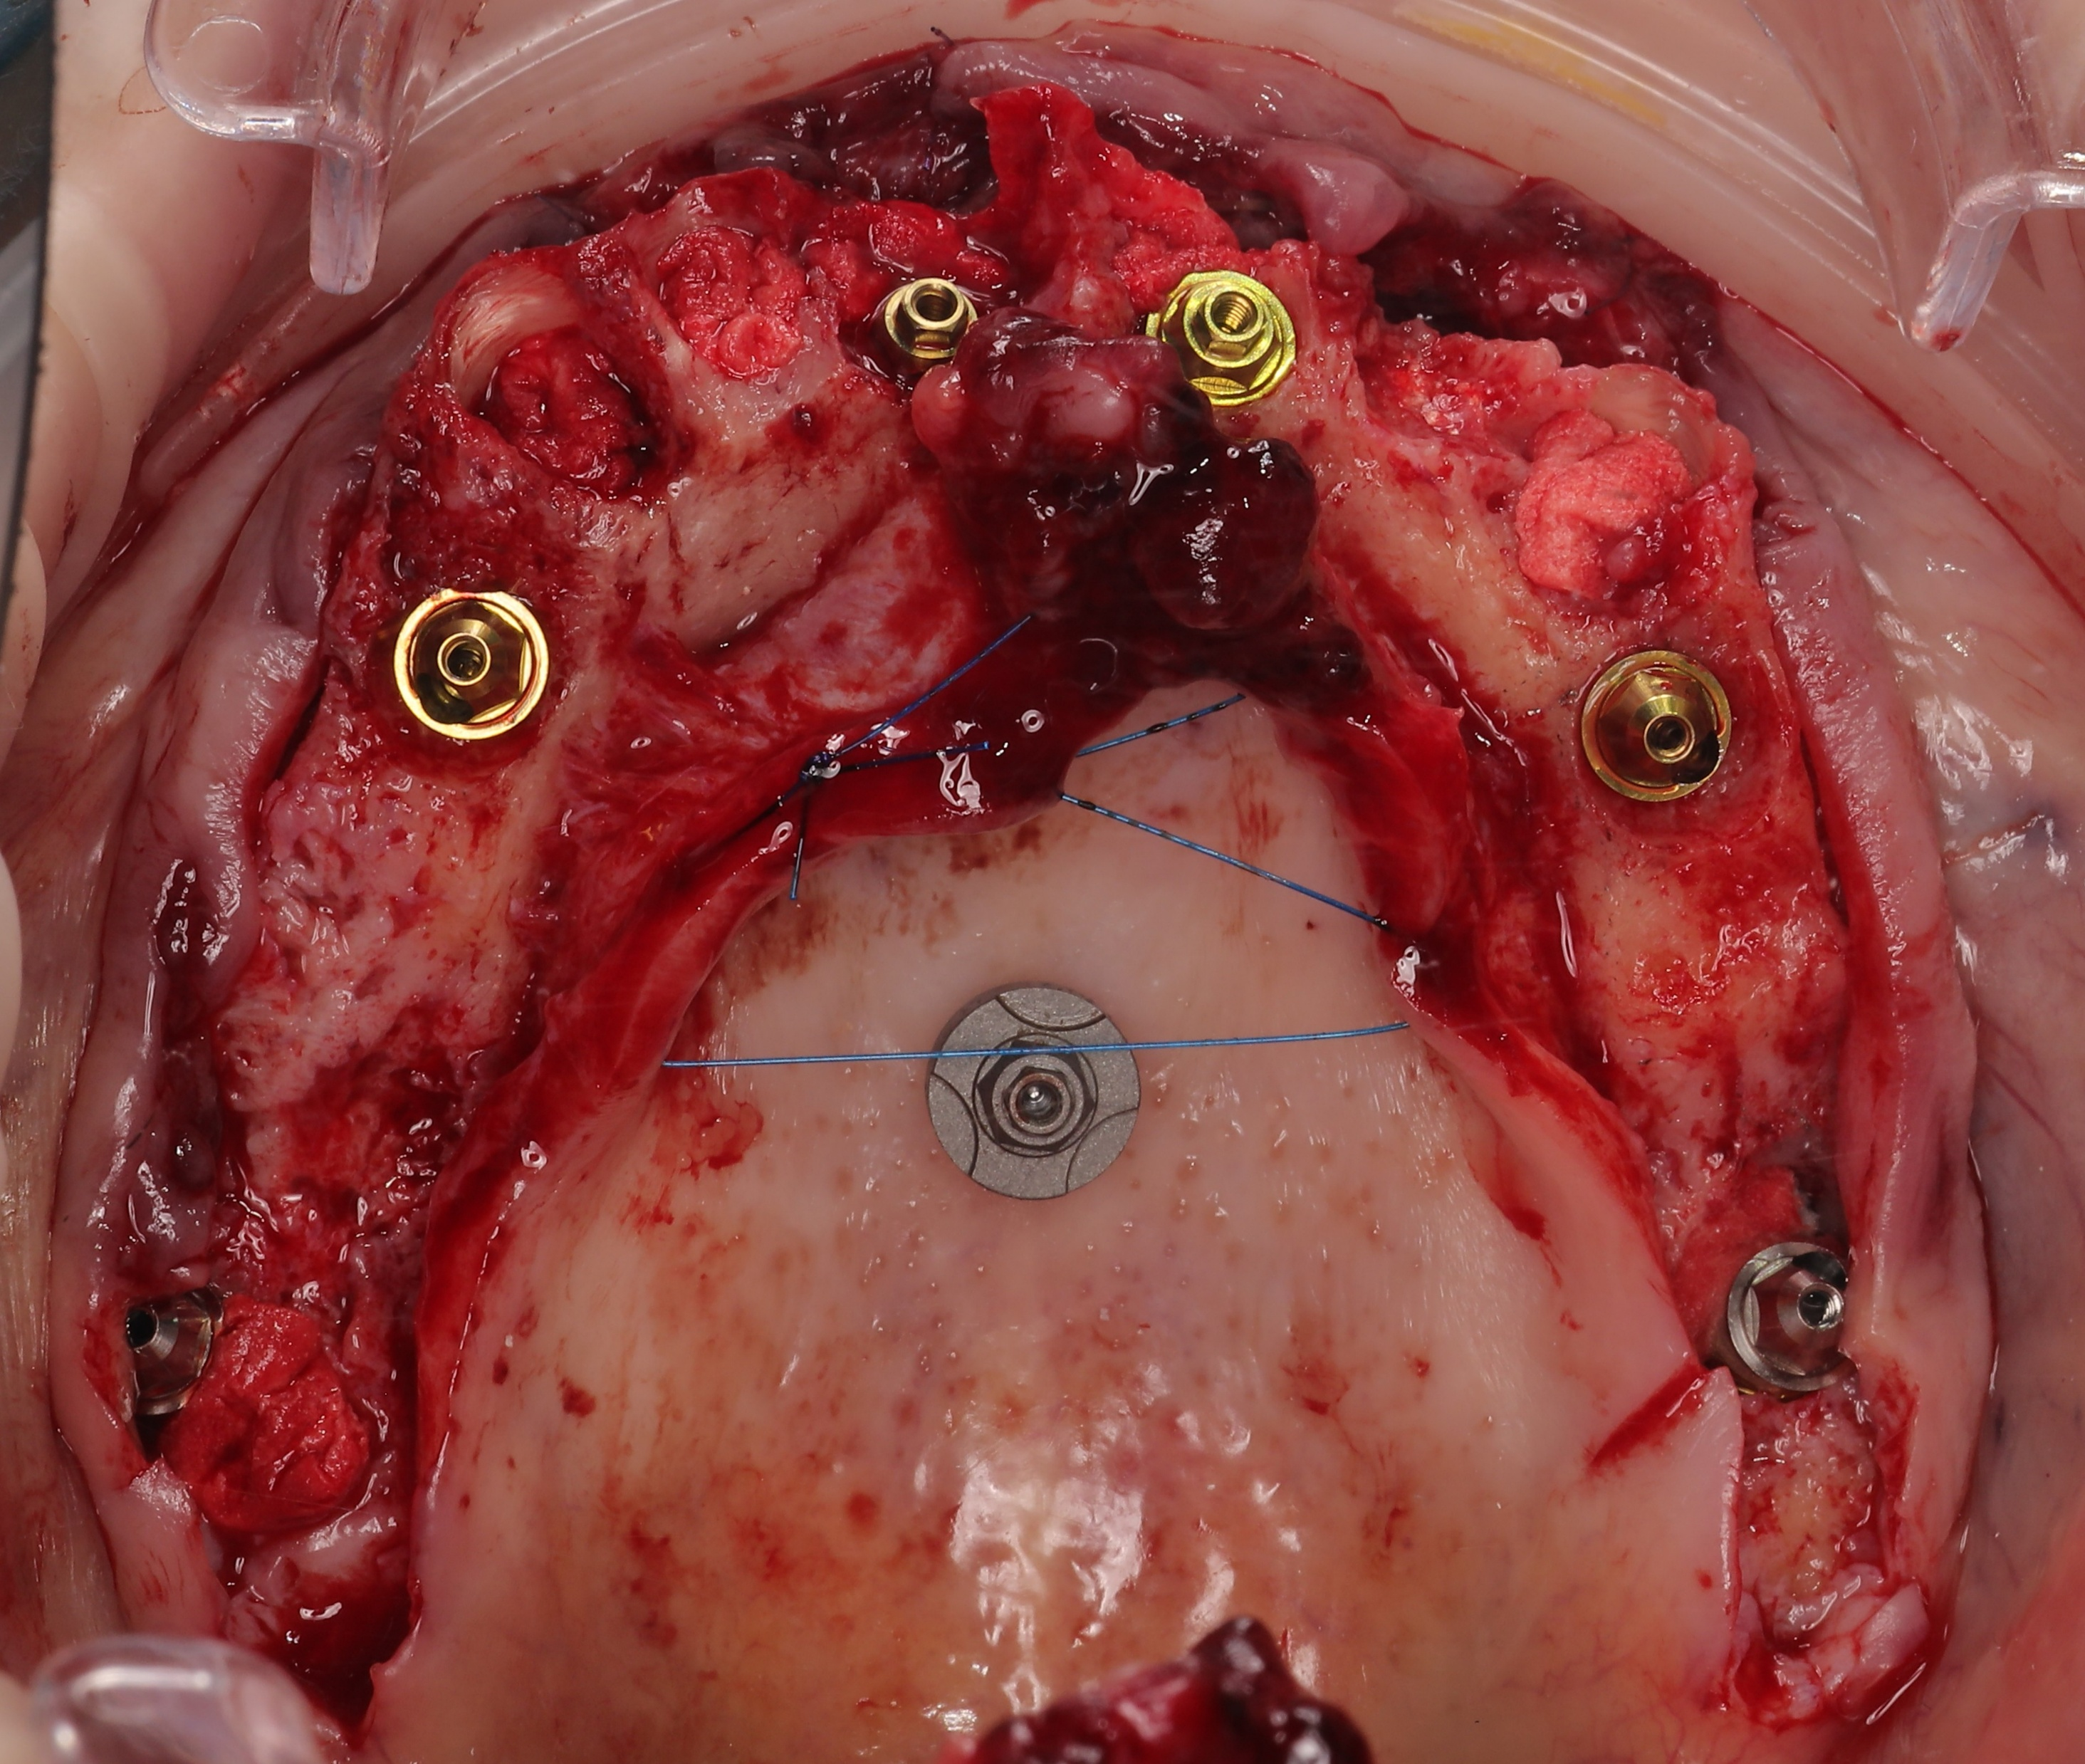

Maxillary :

The surgical phase began with the placement of palatal scan markers for digital alignment, followed by a full-thickness flap elevation. To maintain the buccal ridge profile, the Root Shield technique was performed at sites 13, 12, and 23, where vestibular bone support was sufficient. JDental Icon Plus implants were installed in the remaining sites. To address posterior bone deficiency without sinus augmentation, JDental Paga3 pterygoid implants were placed via a transsinusal approach. The workflow concluded with soft tissue management, forming a critical step in the overall digital dental workflow for full arch dental implants rehabilitation.

Mandibular :

Following marker placement and necessary bone reduction, JDental Icon Plus implants were installed and fitted with Multi-Unit Abutments (MUA). A preliminary suturing was performed to stabilize the site, after which a mandibular IPG scan was executed to capture precise implant positions. The procedure was finalized with the complete closure and suturing of the gingival grafts to ensure optimal soft tissue healing.